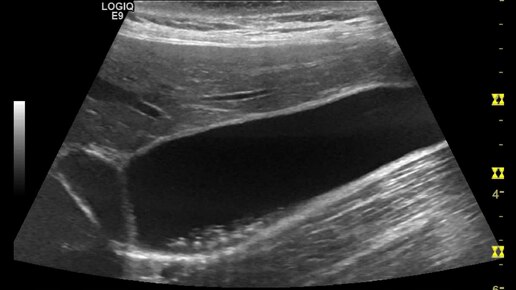

Видео к статье "Клинический случай. Мелкие камни в желчном пузыре"https://dzen.ru/a/Z9U-tccCD2Le53Yr

Ультразвуковые находки от врача УЗД Зорина Я.П.